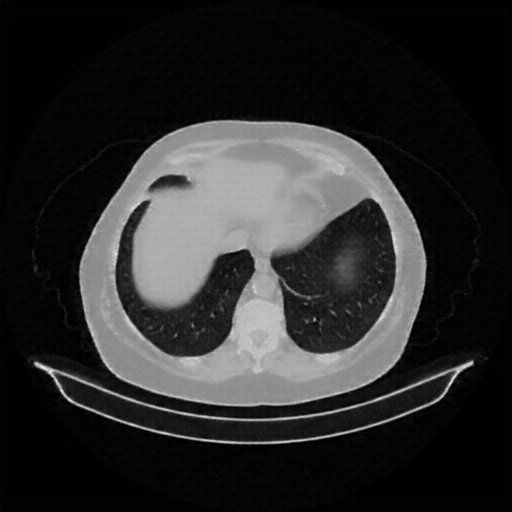

Image Grid

4Γ—3 grid: Rows show different image types (Original NATIVE, Reconstructed NATIVE, Original VENOUS, Generated VENOUS), Columns show windowing techniques (No Window, Lung Window, Mediastinum Window)

Original VENOUS CT scan

Mediastinum window (WL 40, WW 400 β†’ Low βˆ’160, High +240)

Generated VENOUS CT scan (A→B translation)